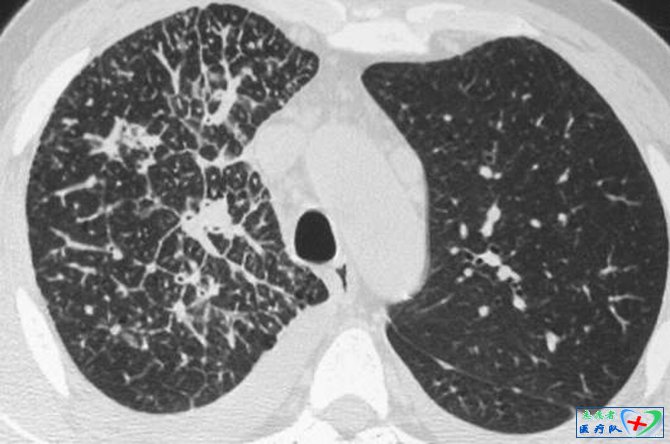

1、串珠样间隔征

胸部高分辨扫描图像上,在肺野周边部或外1/3的肺内小叶间隔表现为不规则、结节状增厚。这是肿瘤细胞在毛细血管或淋巴管内不规则膨胀性生长以及继发的血管周围和间质水肿及纤维化。串珠样间隔征的形成,主要是转移瘤细胞或瘤栓经血型或淋巴播散以及逆行性淋巴管转移在肺周边部的毛细血管或淋巴管内,致使转移灶远测血管或淋巴管扩张;转移灶阻塞引起肺间质水肿;病灶在毛细血管和淋巴管周围不规则生长;长期间质水肿继发纤维增生;周边部毛细血管或淋巴管内肿瘤生长并填充其间。该征主要见于肺转移瘤,其次也见于肺结节病和先天性肺小叶周围纤维化。